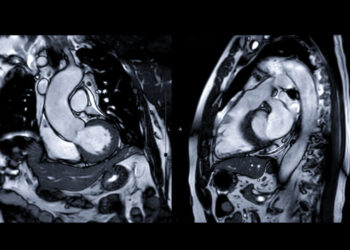

Paragonimozė – reta, tačiau rimta parazitinė liga, kurią sukelia plokščiosios kirmėlės, dar vadinamos paragonimais. Užsikrėsti galima suvalgius termiškai neapdorotos ar...